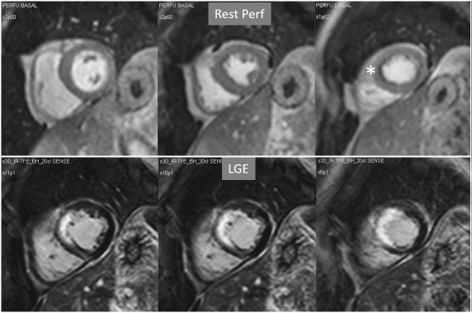

Particularly important, in practice, is the issue of perfusion studies in patients with previous MI. In theory, a basal rest perfusion study should exhibit a reduced signal intensity in the infarcted area, as is the case in the acute phase of a large transmural MI (Fig. 14A). However, not infrequently, the presence and extent of a rest perfusion defect does no correlate with the actual area of necrosis in either, acute (Fig. 14B) or chronic MI (Fig. 15). Signal intensity in areas of previous MI is thus, not dependent merely on the presence of scar tissue, but some other factors lead to differences in CA concentration between MI and remote regions and, in this sense, rest perfusion CMR cannot be equated to SPECT studies, where rest defects are directly related to the presence of infarcted myocardial tissue not amenable to radiotracer uptake [45].

Fig. 15.Rest perfusion in chronic myocardial infarction. Basal rest perfusion study showing a reduced subendocardial septal defect (asterisk) at the apical septum in a patient with an extensive old anteroseptal MI evidenced at LGE.